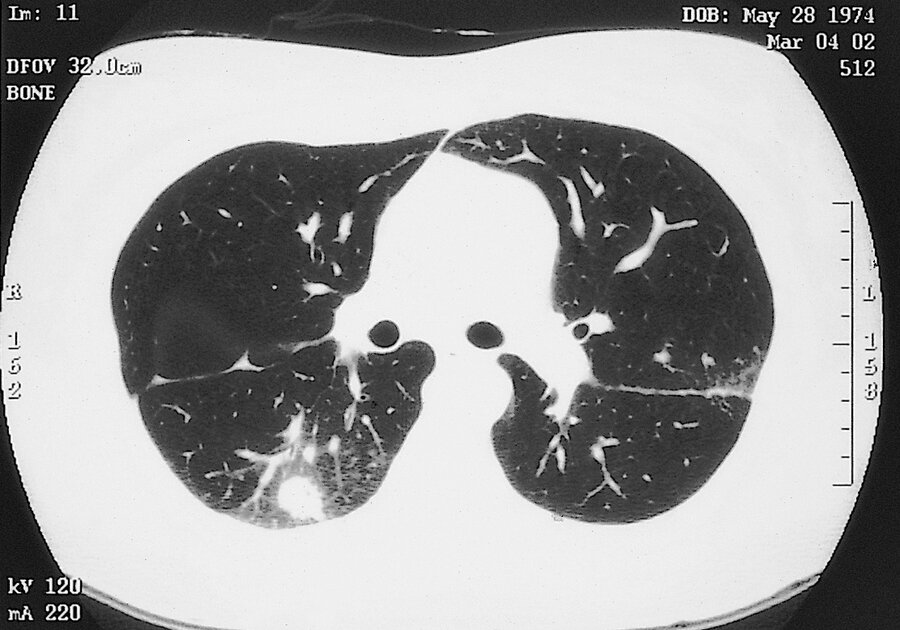

- CT chest can reveal septic emboli (nodules, often with a “halo sign”; ) (Figure 19), thromboembolic pulmonary infarction (wedge-shaped peripheral densities), or necrosis with cavitation (air-crescent sign) are typical findings

- “Halo sign,” is an area of low attenuation surrounding a pulmonary nodule that reflects hemorrhage into the adjacent tissues.